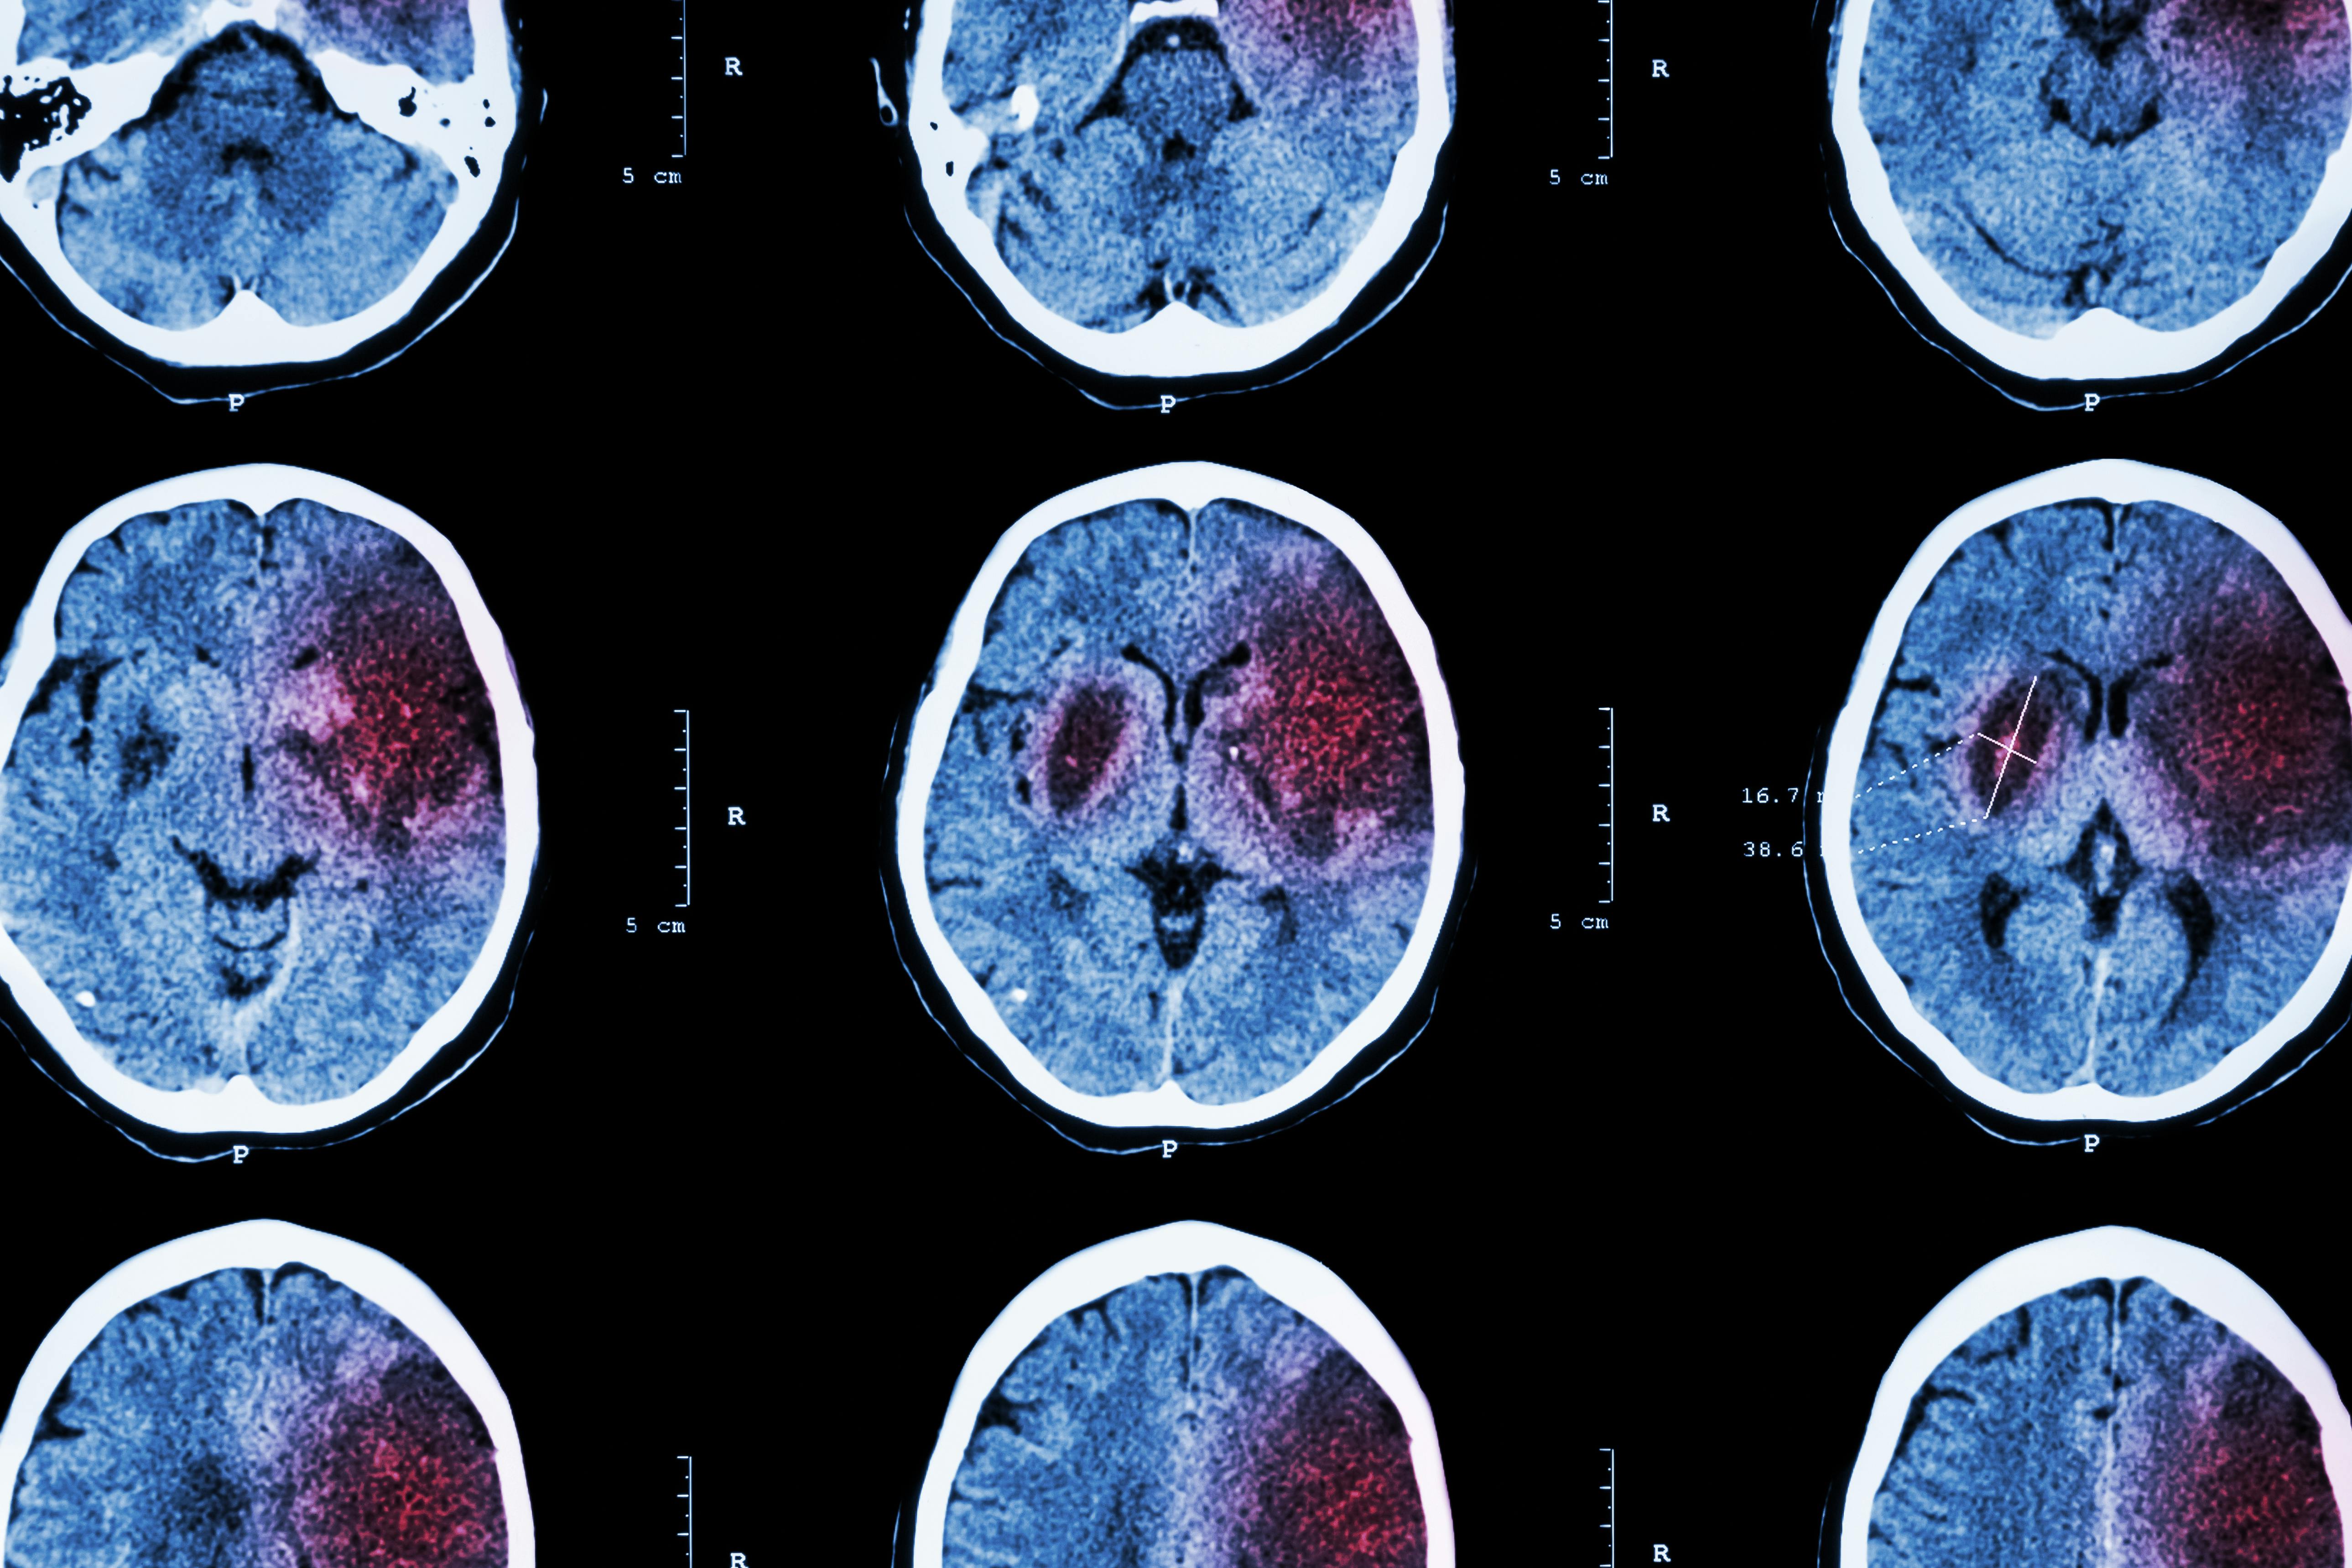

RapidAI specifically “speeds stroke diagnosis and treatment,” analyzing CT scans for “large vessel occlusion” and then sending “images and notifications to clinicians’ mobile devices.” This has helped Henry Ford Health reduce “door-to-treatment time,” among other improvements.

Traditionally, the diagnostic path for suspected stroke included a CT scan, which was then reviewed by a radiologist, neurologist, and neurointerventionalist; RapidAI, however, reduces that process to “minutes.” Alex Chebl, director of the Henry Ford Stroke Center, says median door-to-puncture time has decreased “by about 20 minutes since 2021,” which represents a reduction of about 40%.